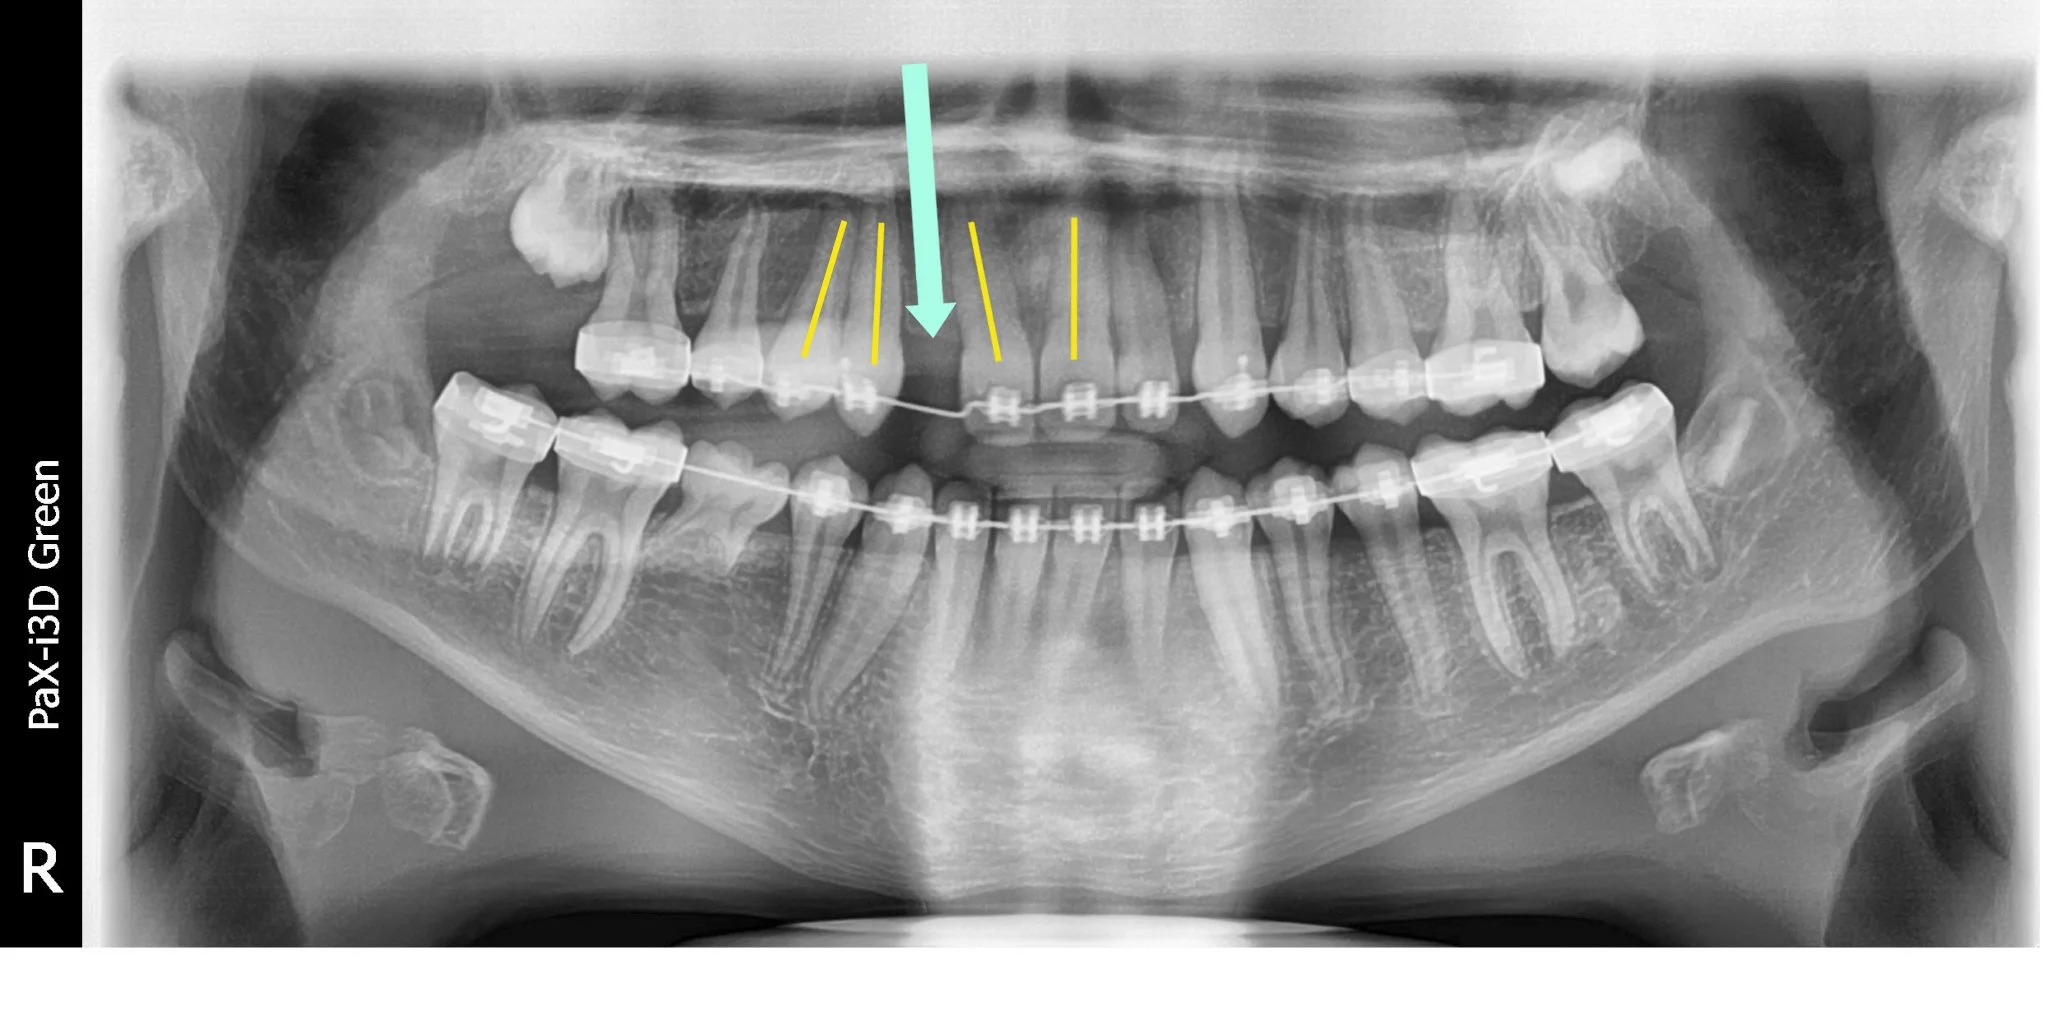

Teeth are leveled and aligned using light and flexible arch wires. This also allows for space to be opened for the missing tooth/teeth.

Once the correct amount of space has been created, a heavy arch wire is placed, and a fake tooth (pontic) is added. This occurs approximately 8-12 months into treatment.

BEFORE

-